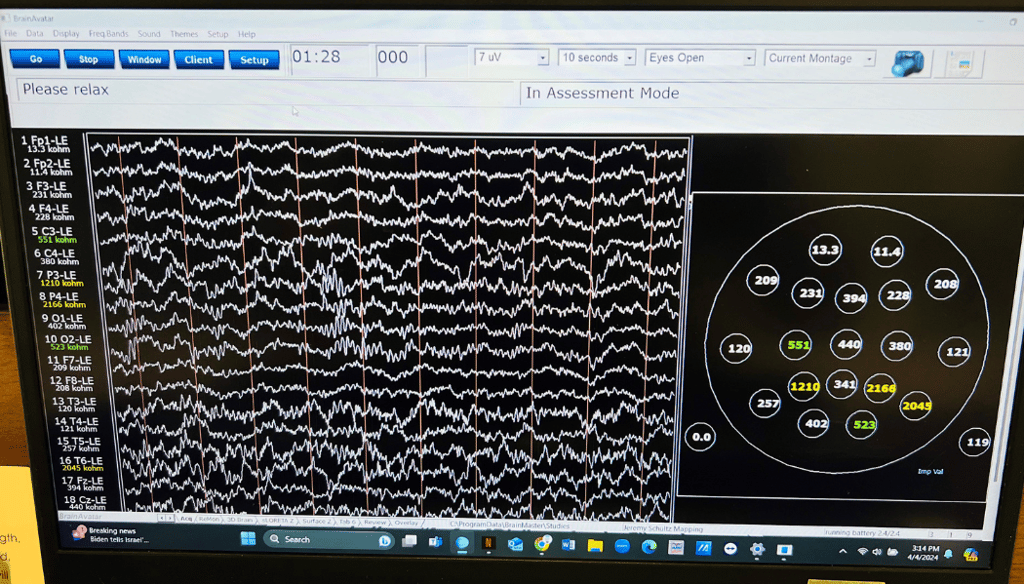

Neurofeedback is a therapeutic technique that aims to train individuals to regulate their brain waves. It involves using real-time displays of brain activity, typically captured through EEG (electroencephalography), to provide feedback on brain function. Here’s how neurofeedback can change brain waves:

1. Feedback Loop: During a neurofeedback session, the individual receives feedback about their brain activity. This is often presented through visual or auditory cues. For example, a person might see a graph of their brain waves or hear sounds that change based on their brain activity.

2. Reinforcement Learning: By providing immediate feedback, neurofeedback encourages the individual to make desired changes in their brain wave patterns. When they produce brain waves associated with relaxation or focus (for example, increasing alpha or beta waves), they may receive positive reinforcement, such as a visual reward or an enjoyable sound.

3. Training Specific Frequencies: Different brain wave patterns are associated with various mental states. Neurofeedback can help individuals learn to enhance specific brain wave frequencies (such as increasing alpha waves for relaxation or beta waves for focus) while reducing unwanted patterns (such as excessive theta waves, which may be linked to distraction).

4. Neuroplasticity: The brain's ability to change and adapt, known as neuroplasticity, allows it to reorganize itself based on experiences. Regular neurofeedback training can promote lasting changes in brain wave patterns, leading to improvements in attention, mood, and overall mental health.

5. Therapeutic Benefits: Research has shown that neurofeedback can be beneficial for various conditions, including ADHD, anxiety, depression, and PTSD. By optimizing brain wave activity, individuals may experience improvements in cognitive function, emotional regulation, and overall well-being.